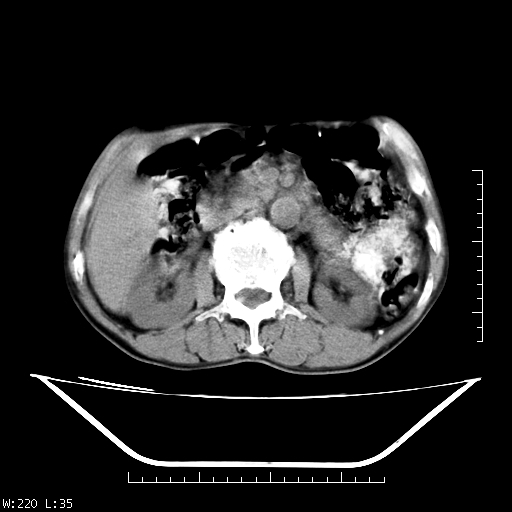

男,70,右上腹痛两月,有乙肝病史,b超提示肝占位,ct如下,请会诊。

肝右叶类圆型密度减低影,密度不均,边界清晰其内可见更低密度影,腹膜后可见小淋巴结肿大,增强扫描动脉期病灶明显强化,静脉期及延时扫描见强化不明显,快进快出表现。

肝右叶占位--考虑为肝癌;

快进快出   典型的原发性肝癌    肝门部见肿大淋巴结

肝癌,腹膜后淋巴转移不除外。